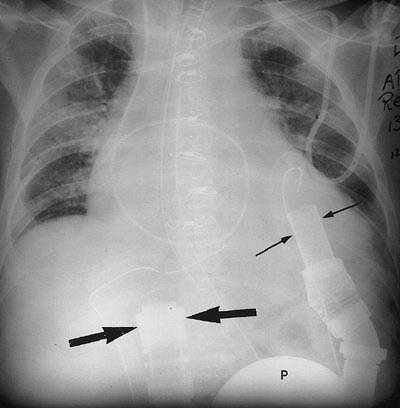

FIGURE 5-17. Left ventricular assist device. AP recumbent chest radiograph shows the inflow cannula (small arrows) within the left ventricle and directed toward the mitral valve, the pump (P), and the radiopaque portion of the outflow cannula (large arrows). The outflow cannula carries blood from the pump to the ascending aorta (the distal portion of the outflow cannula is nonradiopaque). The cardiac silhouette is markedly enlarged in this patient with end-stage heart disease.